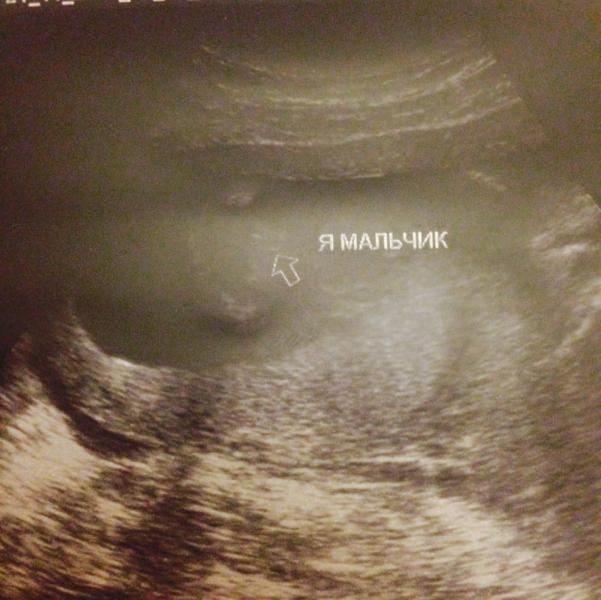

Были сегодня на УЗИ у Бабаевой👍Вежливая , разговорчивая))) Но мой совет лучше ходить с мужьями с ними они приветливей 😆☝️. Пока не началось УЗИ из разговора с ней стала говорить , что спец. УЗИ , которые говорят пол на раннем сроке 12-13 недель просто вводят нас в заблуждение , пол можно определить только после 20 недель, но когда УЗИ стали делать первым делом сказала , что в нас мальчик😂😂😂 и даже сфоткала наше ,, богатство,, правда на фото плохо видно. Потом стала говорить , что все у нас хоро...